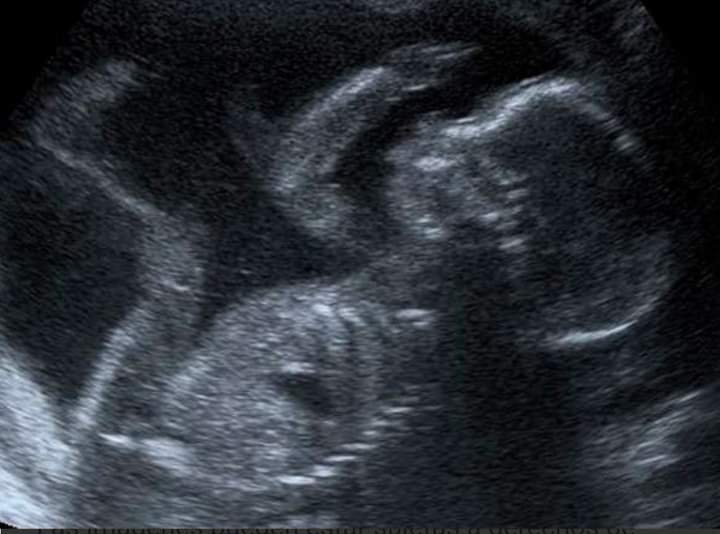

ULTRASON

J'ai fait un vœu et tu es devenu réalité